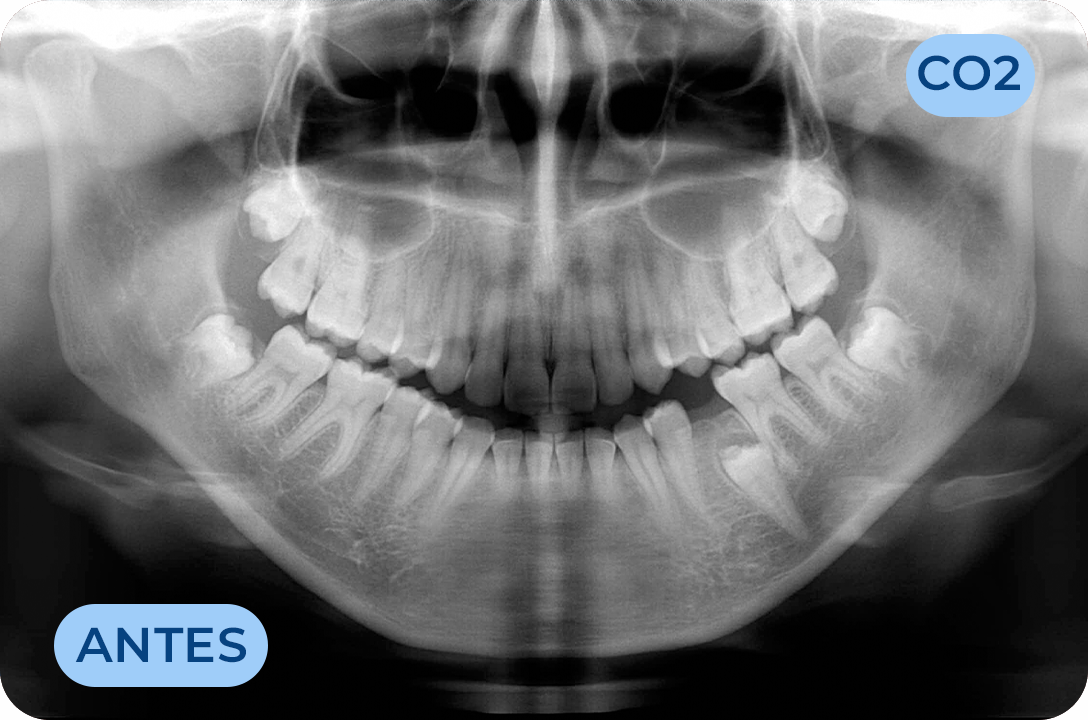

Ortodontia

É a especialidade da Medicina Dentária que se debruça sobre o estudo e correção das más posições dentárias e dos maxilares. Atualmente é possível tratar pacientes de todas as idades, no entanto a 1ª consulta deve ser realizada ainda na infância para intercetar eventuais problemas de desenvolvimento esquelético e funcional.